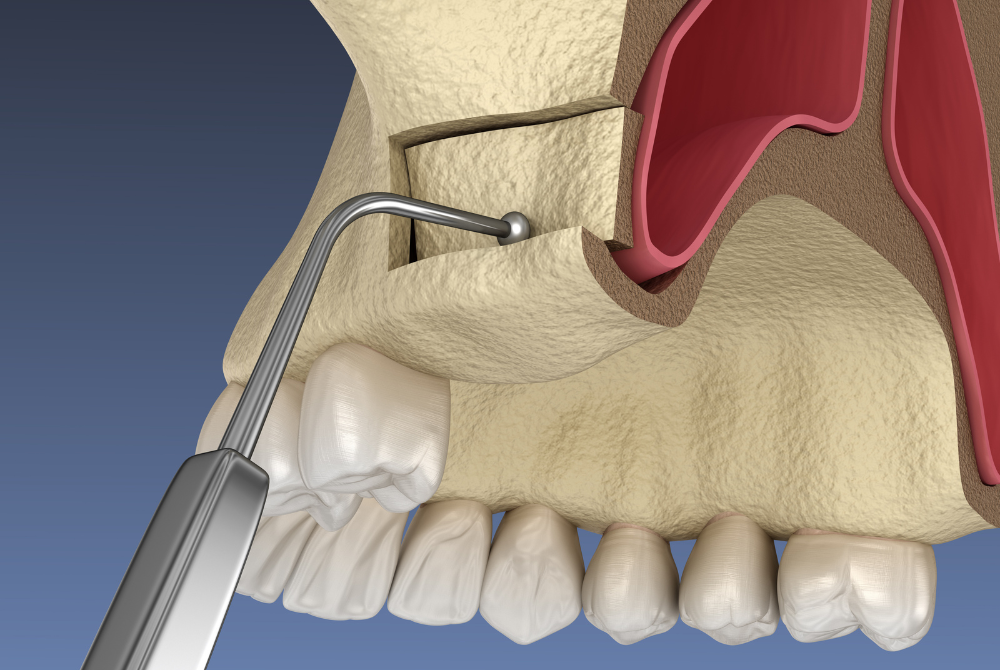

骨が少ないと断られた方でも治療が可能

インプラントをするのには、必要十分な量の顎の骨が必要です。 他院で骨が足りないことを理由に、インプラントを断られた方でも、骨造成治療を行うことでインプラント治療が可能になることがあります。

上顎の奥歯部分で骨の高さが少し不足している場合に行う方法です。 上顎洞という空洞の底を持ち上げ、そこに骨補填材を入れることで骨の厚みを確保します。

• サイナスリフト

上顎奥歯の骨が大きく不足している場合に行う方法です。 上顎洞の側面からアプローチし、しっかりと骨の量を増やします。重度の骨吸収がある方にも対応できる治療法です。

• GBR(骨誘導再生法)

骨の幅や高さが足りない部分に骨補填材を入れ、特殊な膜で覆うことで骨の再生を促す方法です。インプラントを埋入する部位に必要な骨量をピンポイントで増やすことができます。